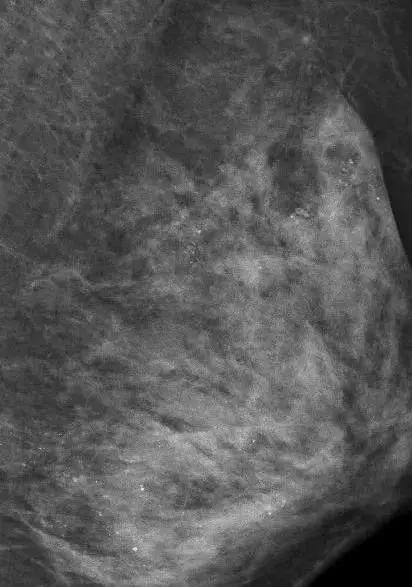

医生在对她的左侧乳房进行乳腺X线检查时,发现里面全部都是细小如沙子一样的钙化灶,布满整个乳腺。

▲在X光片下,朱女士的乳腺里满是星星点点的钙化灶